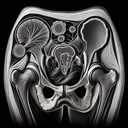

МРТ кульшових суглобів

Магнітно-резонансна томографія (МРТ) кульшових суглобів — це неінвазивний метод діагностики, який використовується для отримання детальних зображень м'яких тканин, хрящів, кісток та суглобів. Ця процедура допомагає лікарям виявити патології, такі як пошкодження зв’язок, наявність артриту, дисплазію, набряки, пухлини або інфекції у кульшових суглобах. ### Переваги: - **Висока точність:** Дає змогу отримати детальні зображення суглобів і прилеглих структур...